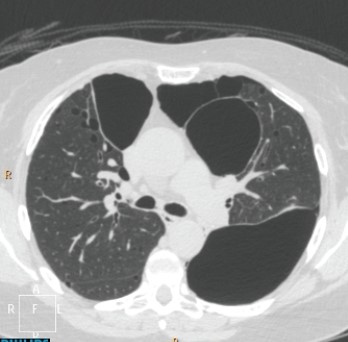

The axial CT shown depicts that this patient has which disease?